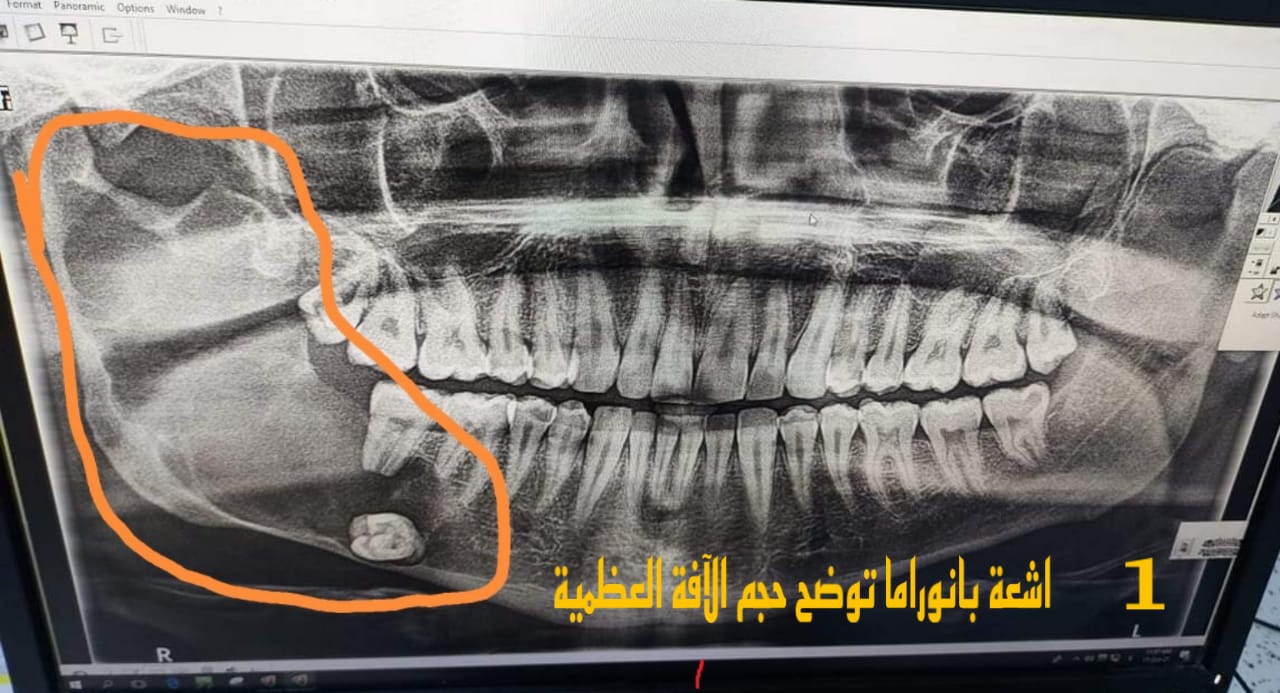

حيث اكد استاذ المادة واخصائي جراحة الوجه والفكين ان المريض كان يعاني من آفة عظمية كبيرة في الفك الاسفل وكان بصدد إجراء العملية في احد المستشفيات تحت البنج العام ولكن بعد أن قام بمراجعة قسم جراحة الوجه والفكين في المستشفى التعليمي لكلية طب الأسنان وبعد إجراء الفحوصات السريرية والشعاعية كافة تقرر إجراء العملية في صالة عمليات القسم وتحت البنج الموضعي واعتبار العملية جزء من المنهاج التدريبي لطلبة المرحلة الخامسة الذين أبدوا حماساً شديداً لحضور العملية، مضيفاً بان اجراء مثل هكذا عمليات كبرى في المستشفى التعليمي هو دليل على الامكانيات المتطورة للقسم في ظل الدعم المستمر من قبل رئيس الجامعة الاستاذ الدكتور وعد محمود رؤوف وان هذه العملية تُعد خطوة أولى في طريق تطوير القسم والخطة القادمة ستكون بإنشاء مركز استشاري لجراحة الوجه والفكين في الكلية ان شاء الله خصوصاً وان هذا الاختصاص يُعدُّ نادراً في عموم محافظة صلاح الدين.